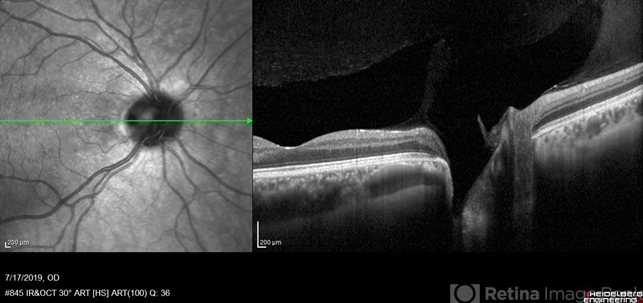

- optical coherence tomography (OCT), optic pit

- Heidelberg Spectralis 2

- Fundus photograph of 38-year-old healthy man with right optic disc pit, who recently noticed slightly blurred vision in right eye while closing the left eye. BCVA was 20/25 in OD and 20/20 in OS. IOP was 15mmHg OD and 14 mmHg OS. Right fundus exam showed small optic disc pit near the temporal rim of optic disc with abnormal reflex of nasal macula. Left fundus was normal. Late FA of right optic disc showed no leakage or staining of optic disc. Macular OCT showed normal foveal contour with no subretinal fluid or macular edema. There was significant reduction in RNFL thickness in the temporal sector in right eye. Coloboma is clearly seen on vertical OCT scan as well as horizontal scans through right optic pit.